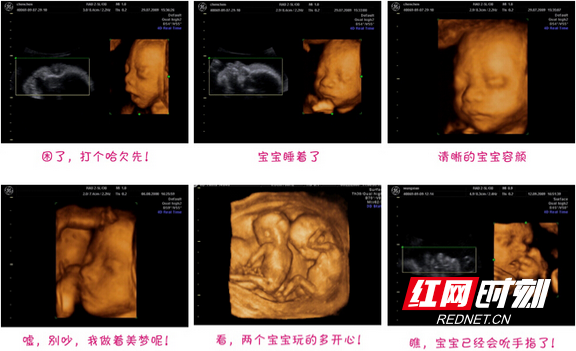

林志颖陪老婆做产检 晒b超照双胞胎很健康

3年不孕到万安2个月怀上双胞胎幸孕妈妈哭了还好我没放弃

少女在网络上晒出的b超证明原标题:少女人流前晒b超:舍不得这对双胞胎